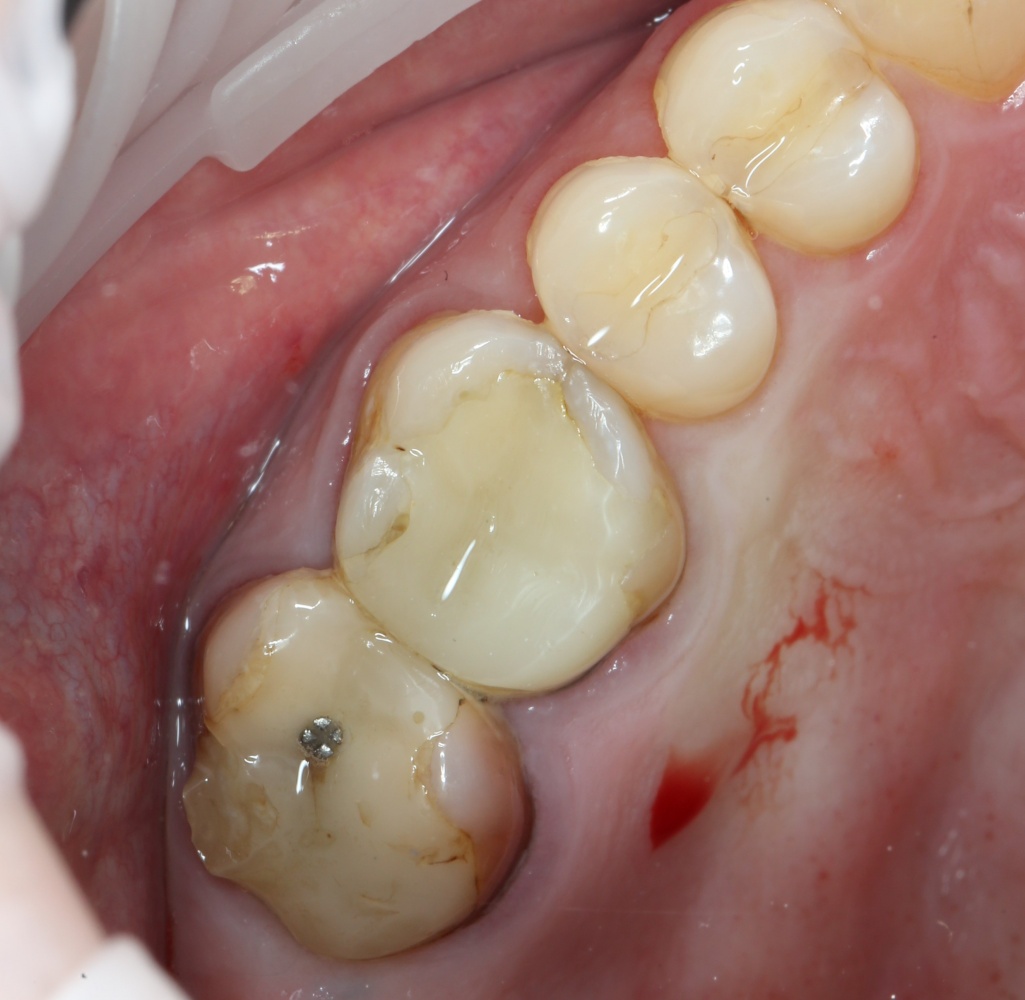

Устанавливается имплантат Astratech (Dentsply Implants):

Для аугментации также используем Bio-Oss Collagen 100 mg, нарезаем его по размеру с помощью скальпеля и позиционируем в лунках щечных корней:

На имплантат ставим формирователь, ушиваем лунку. Напомню, что любой биоматериал должен быть герметично запечатан в ране (фактор успеха III). В противном случае, от него больше вреда, чем пользы:

Совсем уж стягивать края раны не нужно (если бы мы использовали обычный Bio-Oss, то это было бы необходимо). Отличие Bio-Oss Collagen еще и в том, что он не размывается при кровотечении.